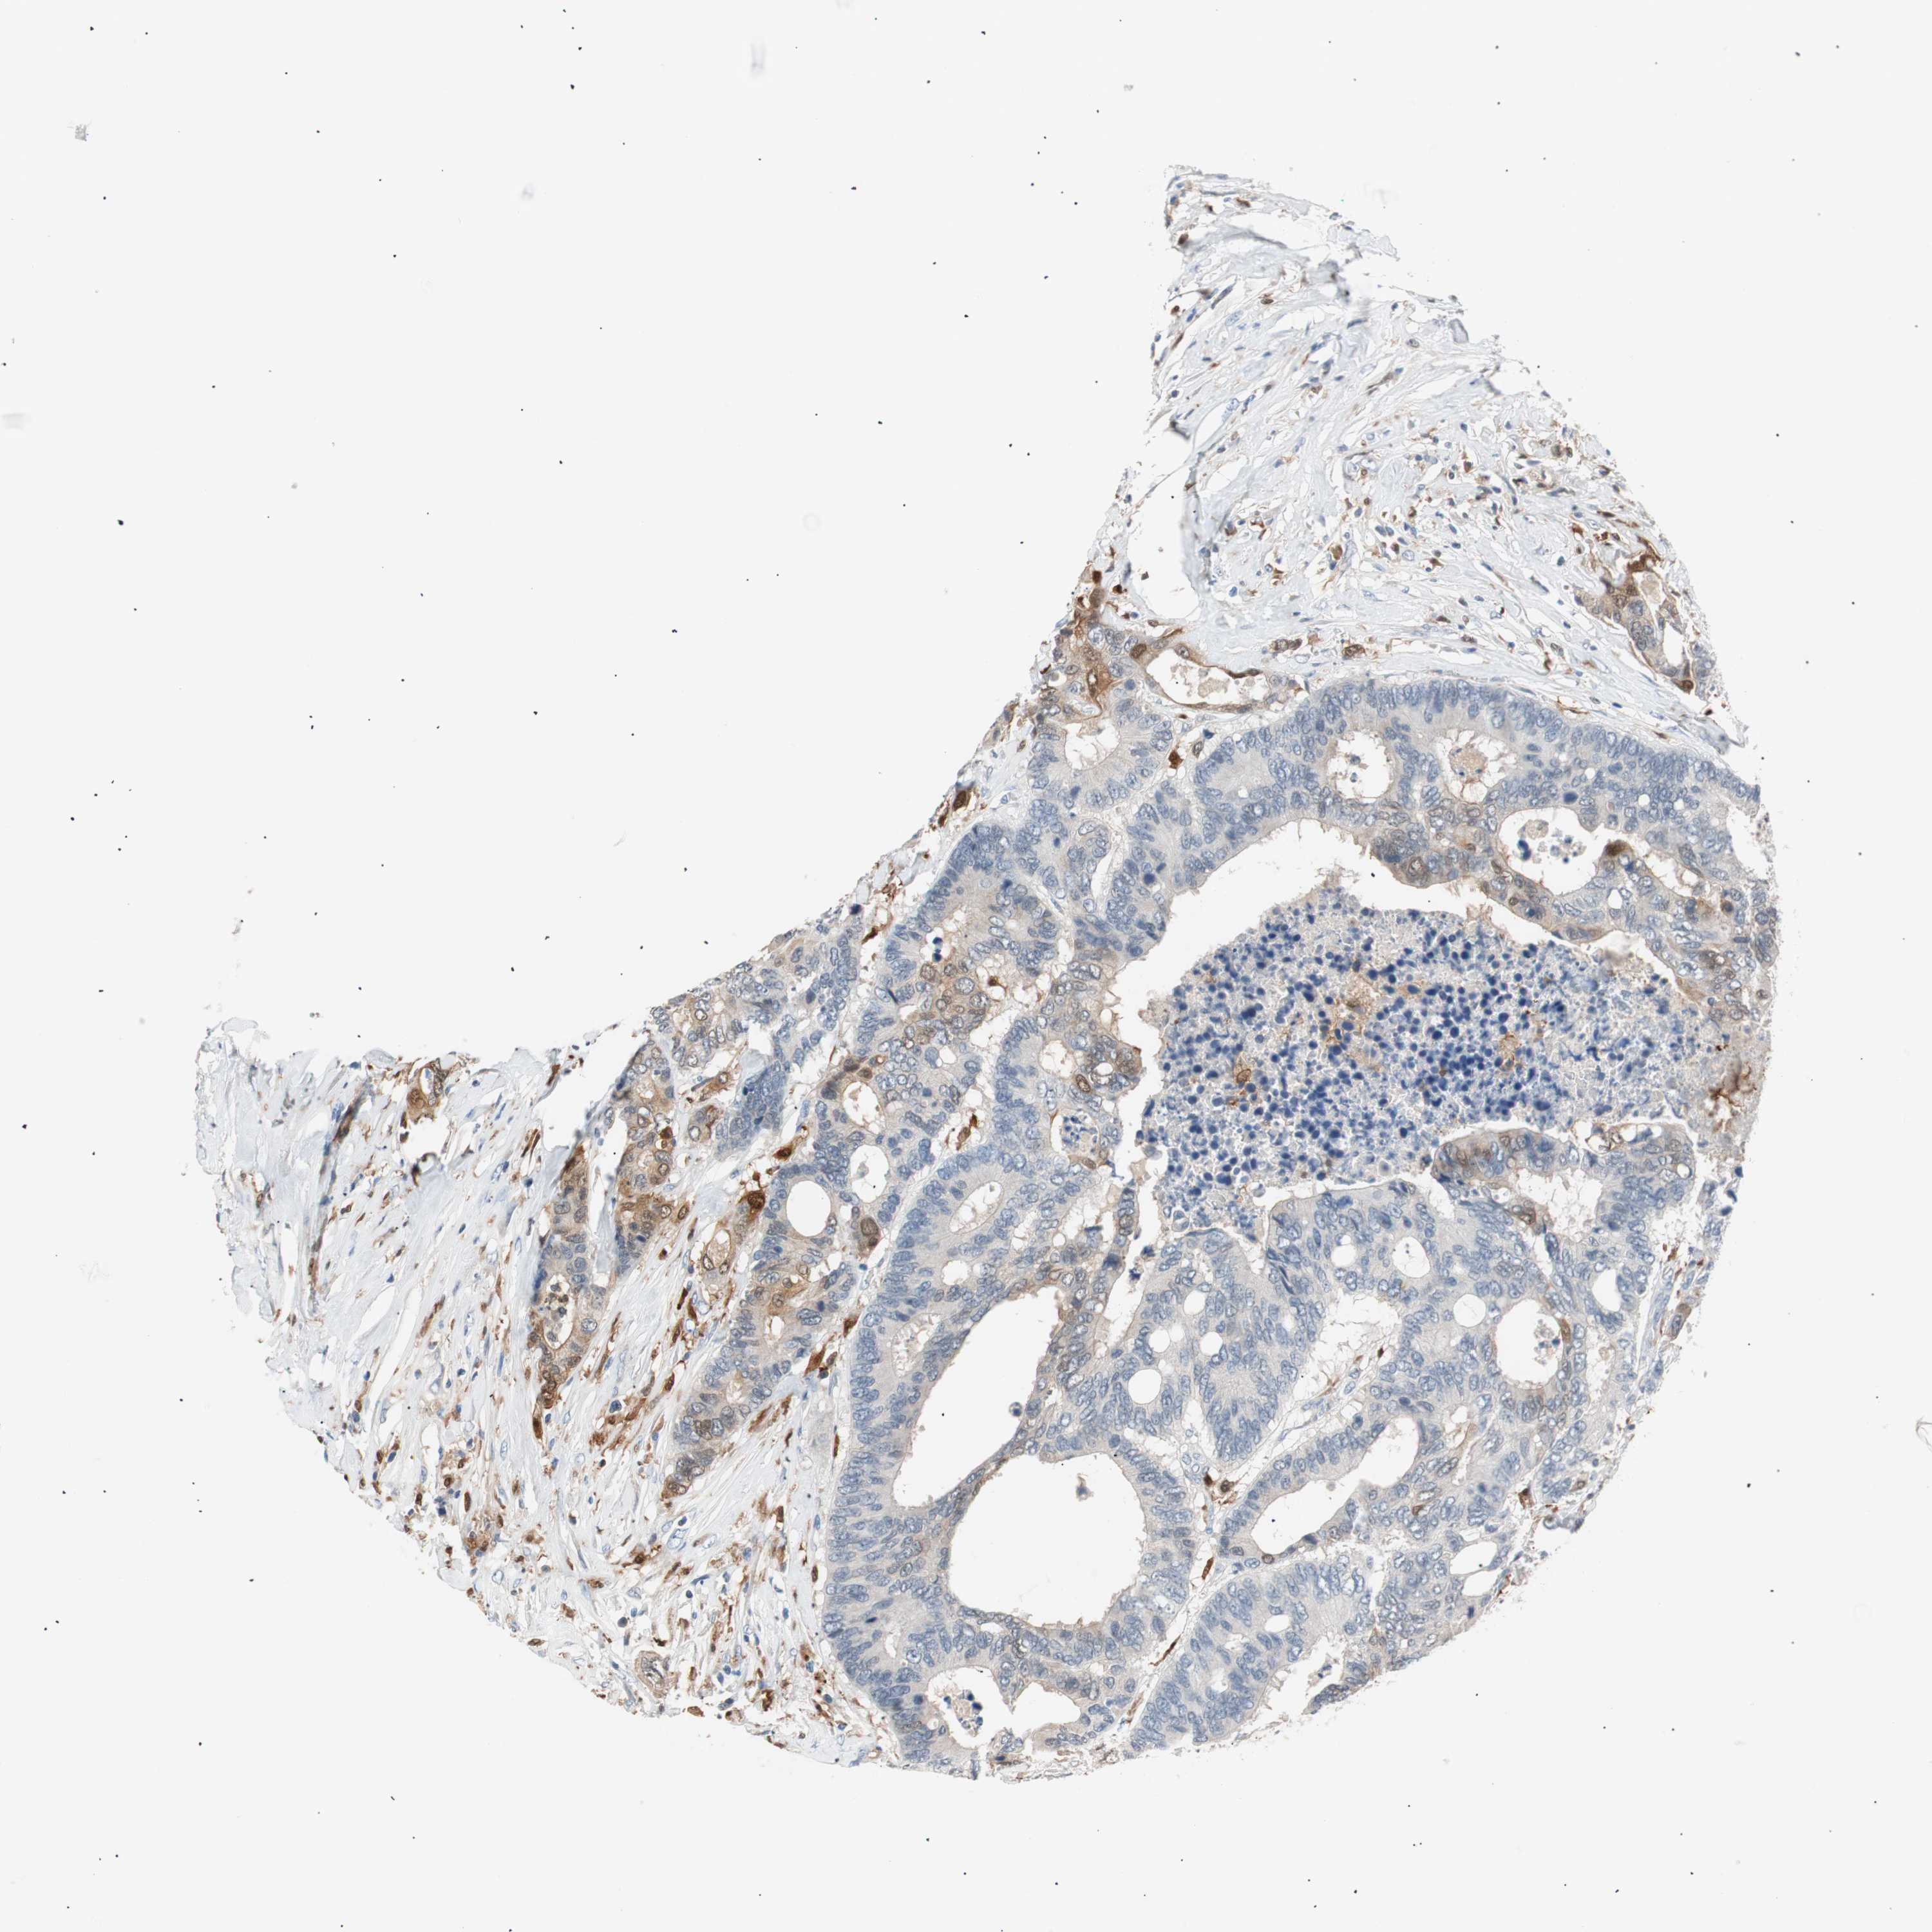

CANCER COLORECTAL CANCER Show tissue menu

Colorectal cancer

Human cancer